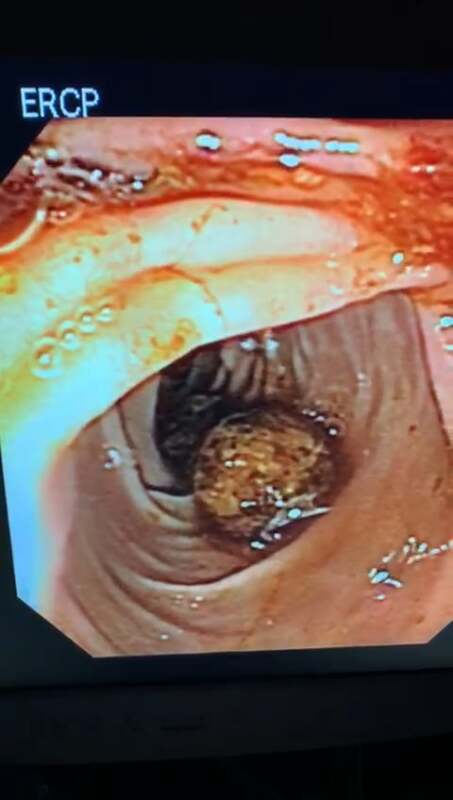

Medicos Cirujanos > Endoscopistas